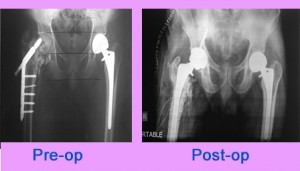

Total HIP Replacement

THR following Surgically Intervened Fracture acetabulum with Implant in situ.

45 years old gentleman operated case of fracture acetabulum with ORIF with plating done in 2008. Patient now presented with pain around left hip and difficulty in walking.

On examination patient had grossly decreased movement at left hip. Radiographically suggestive of secondary ... Read more..